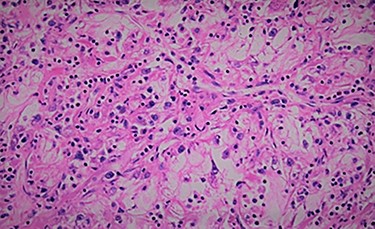

We report the case of 47-year-old men, with a chronic renal failure, who had been operated on 3 years previously for a total left radical nephrectomy for clear cell renal cancer of stage pT3G1N0M0. During the follow-up of the patient, a routine cancer screening with ultrasound revealed a mass in the spleen of about 4 cm of diameter. Laboratory investigations were normal apart from known renal failure (Table 1). Due to known chronic kidney disease and allergy to Iodinated contrast media, an abdominal magnetic resonance imaging (MRI) confirmed the presence of a splenic lesion (Fig. 1). Based on these radiological findings, the splenic mass was diagnosed as a suspicious metastatic lesion. An open splenectomy was performed. The patient recovered uneventfully and was discharged 5 days after surgery. He received pneumococcal, meningococcal and Haemophilus influenzae vaccine. Histologic analysis of the lesion confirmed the presence of clear cell renal cancer metastasis (Fig. 2). The patient was referred to the oncology department for adjuvant treatment with sunitinib. His follow up consisted on abdominal ultrascan (US) every 3 months and MRI at 6 and 12 months from surgery. After 36 months, the patient is doing well with no signs of tumor recurrence.

The definitive diagnosis is based on a histological examination. The cellular diagnosis can be made by using percutaneous biopsy (using US or CT guidance) [5, 6] or endoscopic fine needle aspiration [7]. Surgery for splenic metastasis of kidney cancer is recommended for a palliative purpose and prevention of future complications. In these cases, an adjuvant therapy is recommended but it is effective in only about 10% of patients [8]. The prognosis, if the metastases are multiple is unfavorable, while if it is isolated the surgery, is the best treatment. If a complete resection of the metastasis is achieved the prognosis is favorable [9]. Our patient underwent an open splenectomy without morbidity and was referred to the oncology department for adjuvant treatment with sunitinib. Three years the patient is doing well with no signs of tumor recurrence.